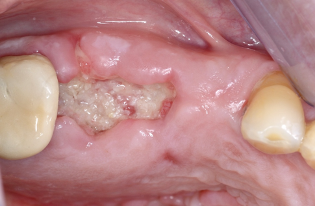

1. Η περιοχή της εξαγωγής με μόσχευμα.